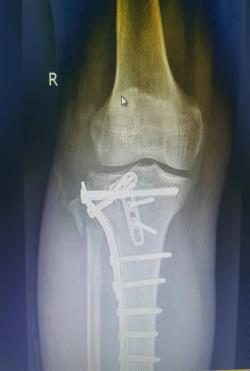

该科擅长对膝关节严重创伤(包括股骨远端骨折、髌骨骨折、胫骨平台骨折等)、膝骨关节炎阶梯化治疗、保膝治疗、膝关节微创单髁置换术、全膝关节置换术、膝关节翻修术具有丰富的临床诊疗经验,追求微创、无痛、快速康复。